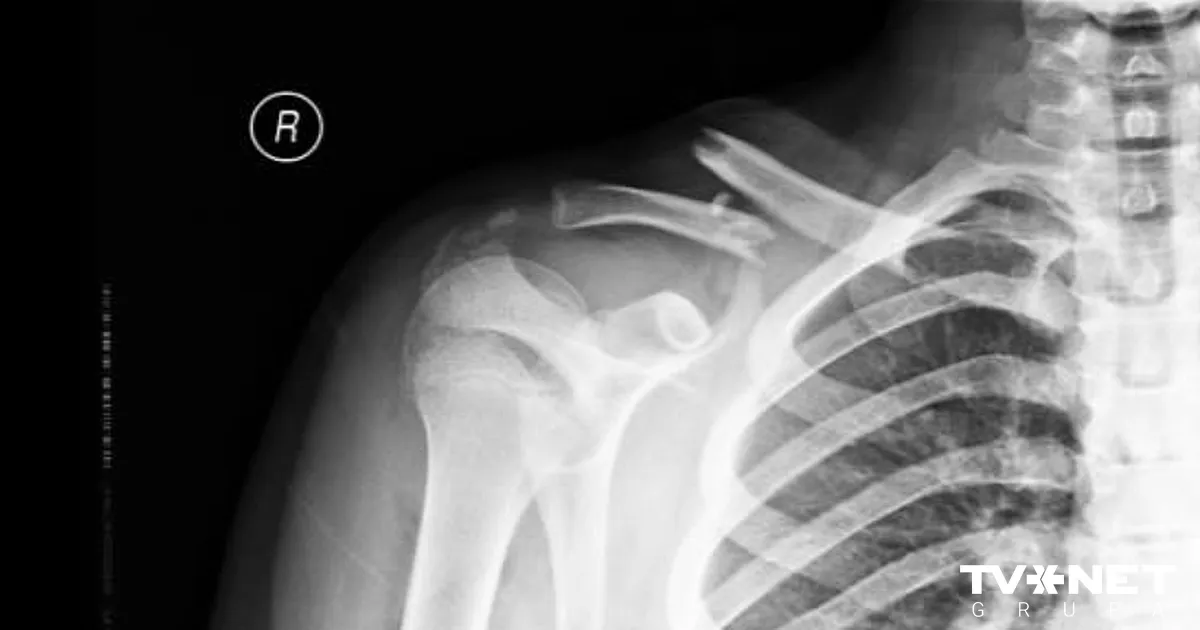

No 360 atslēgas kaula lūzumiem BKUS pērn operēts tikai viens. TVNET+ skaidro, kuros gadījumos to operē un kāpēc vecāki pašrocīgi meklē ķirurgus arī privātās iestādēs.